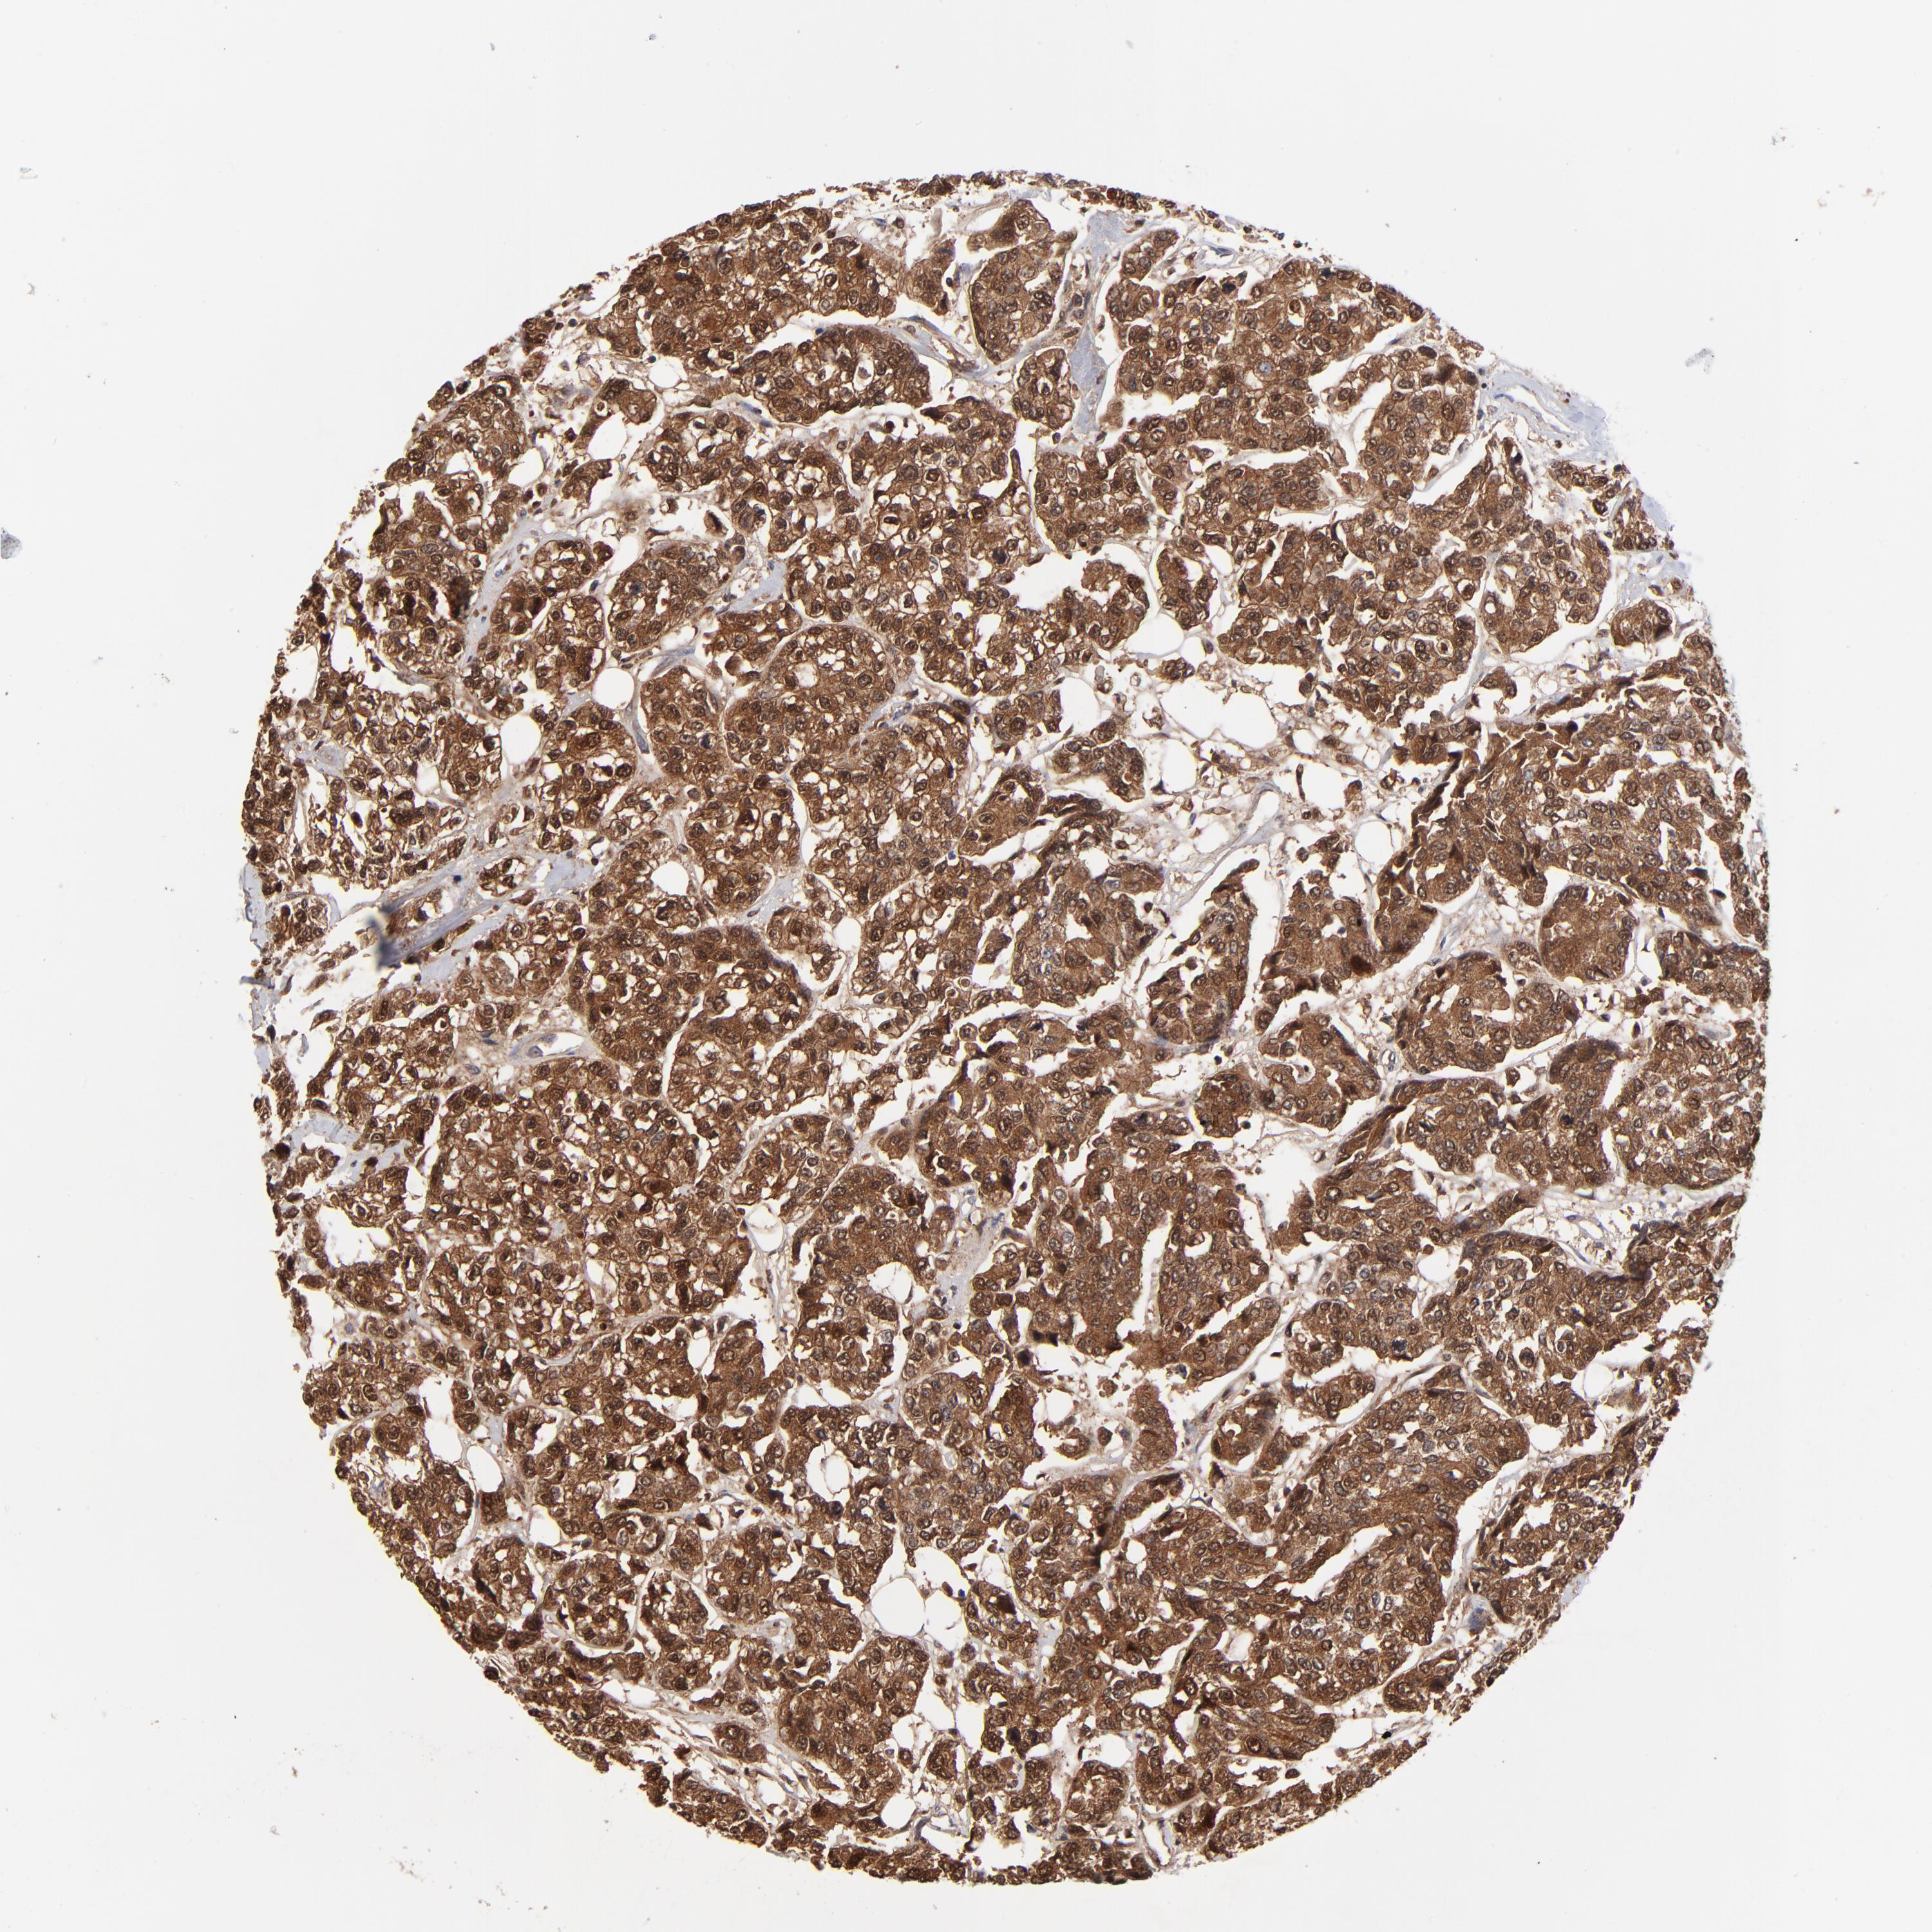

CANCER BREAST CANCER Show tissue menu

Breast cancer

Human cancer

DCTPP1 is potential prognostic, high expression is unfavorable in Breast Invasive Carcinoma (TCGA)